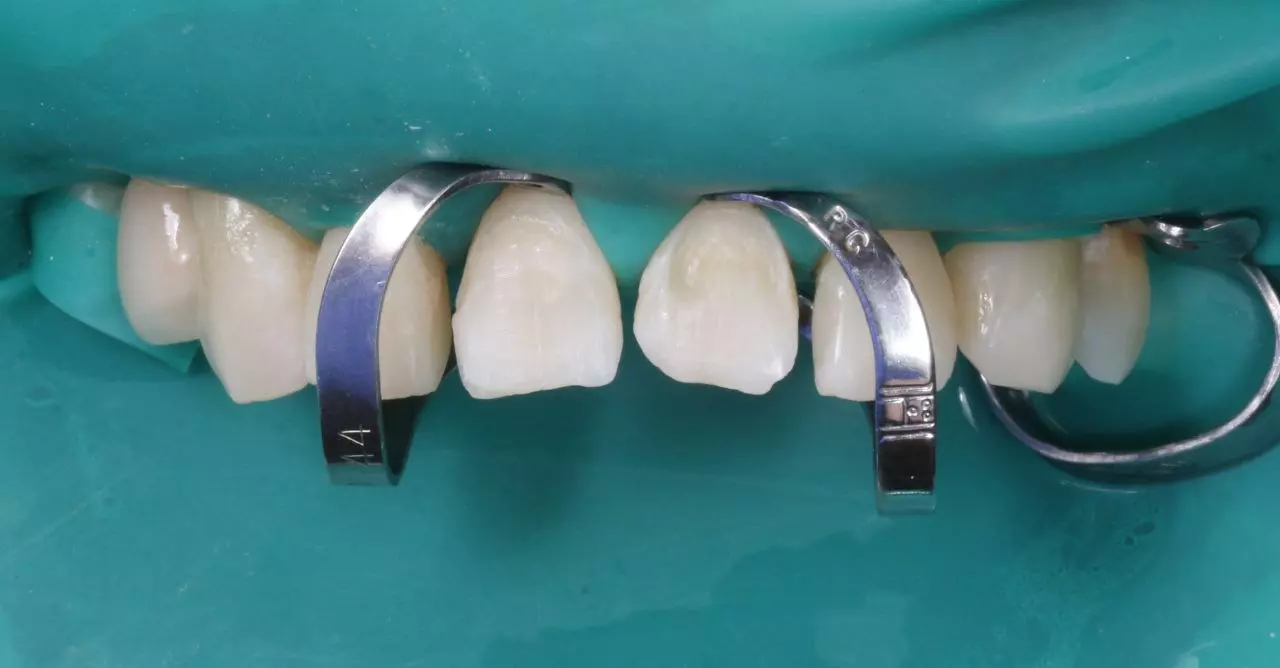

Художня реставрація

Художня реставрація 21.22.